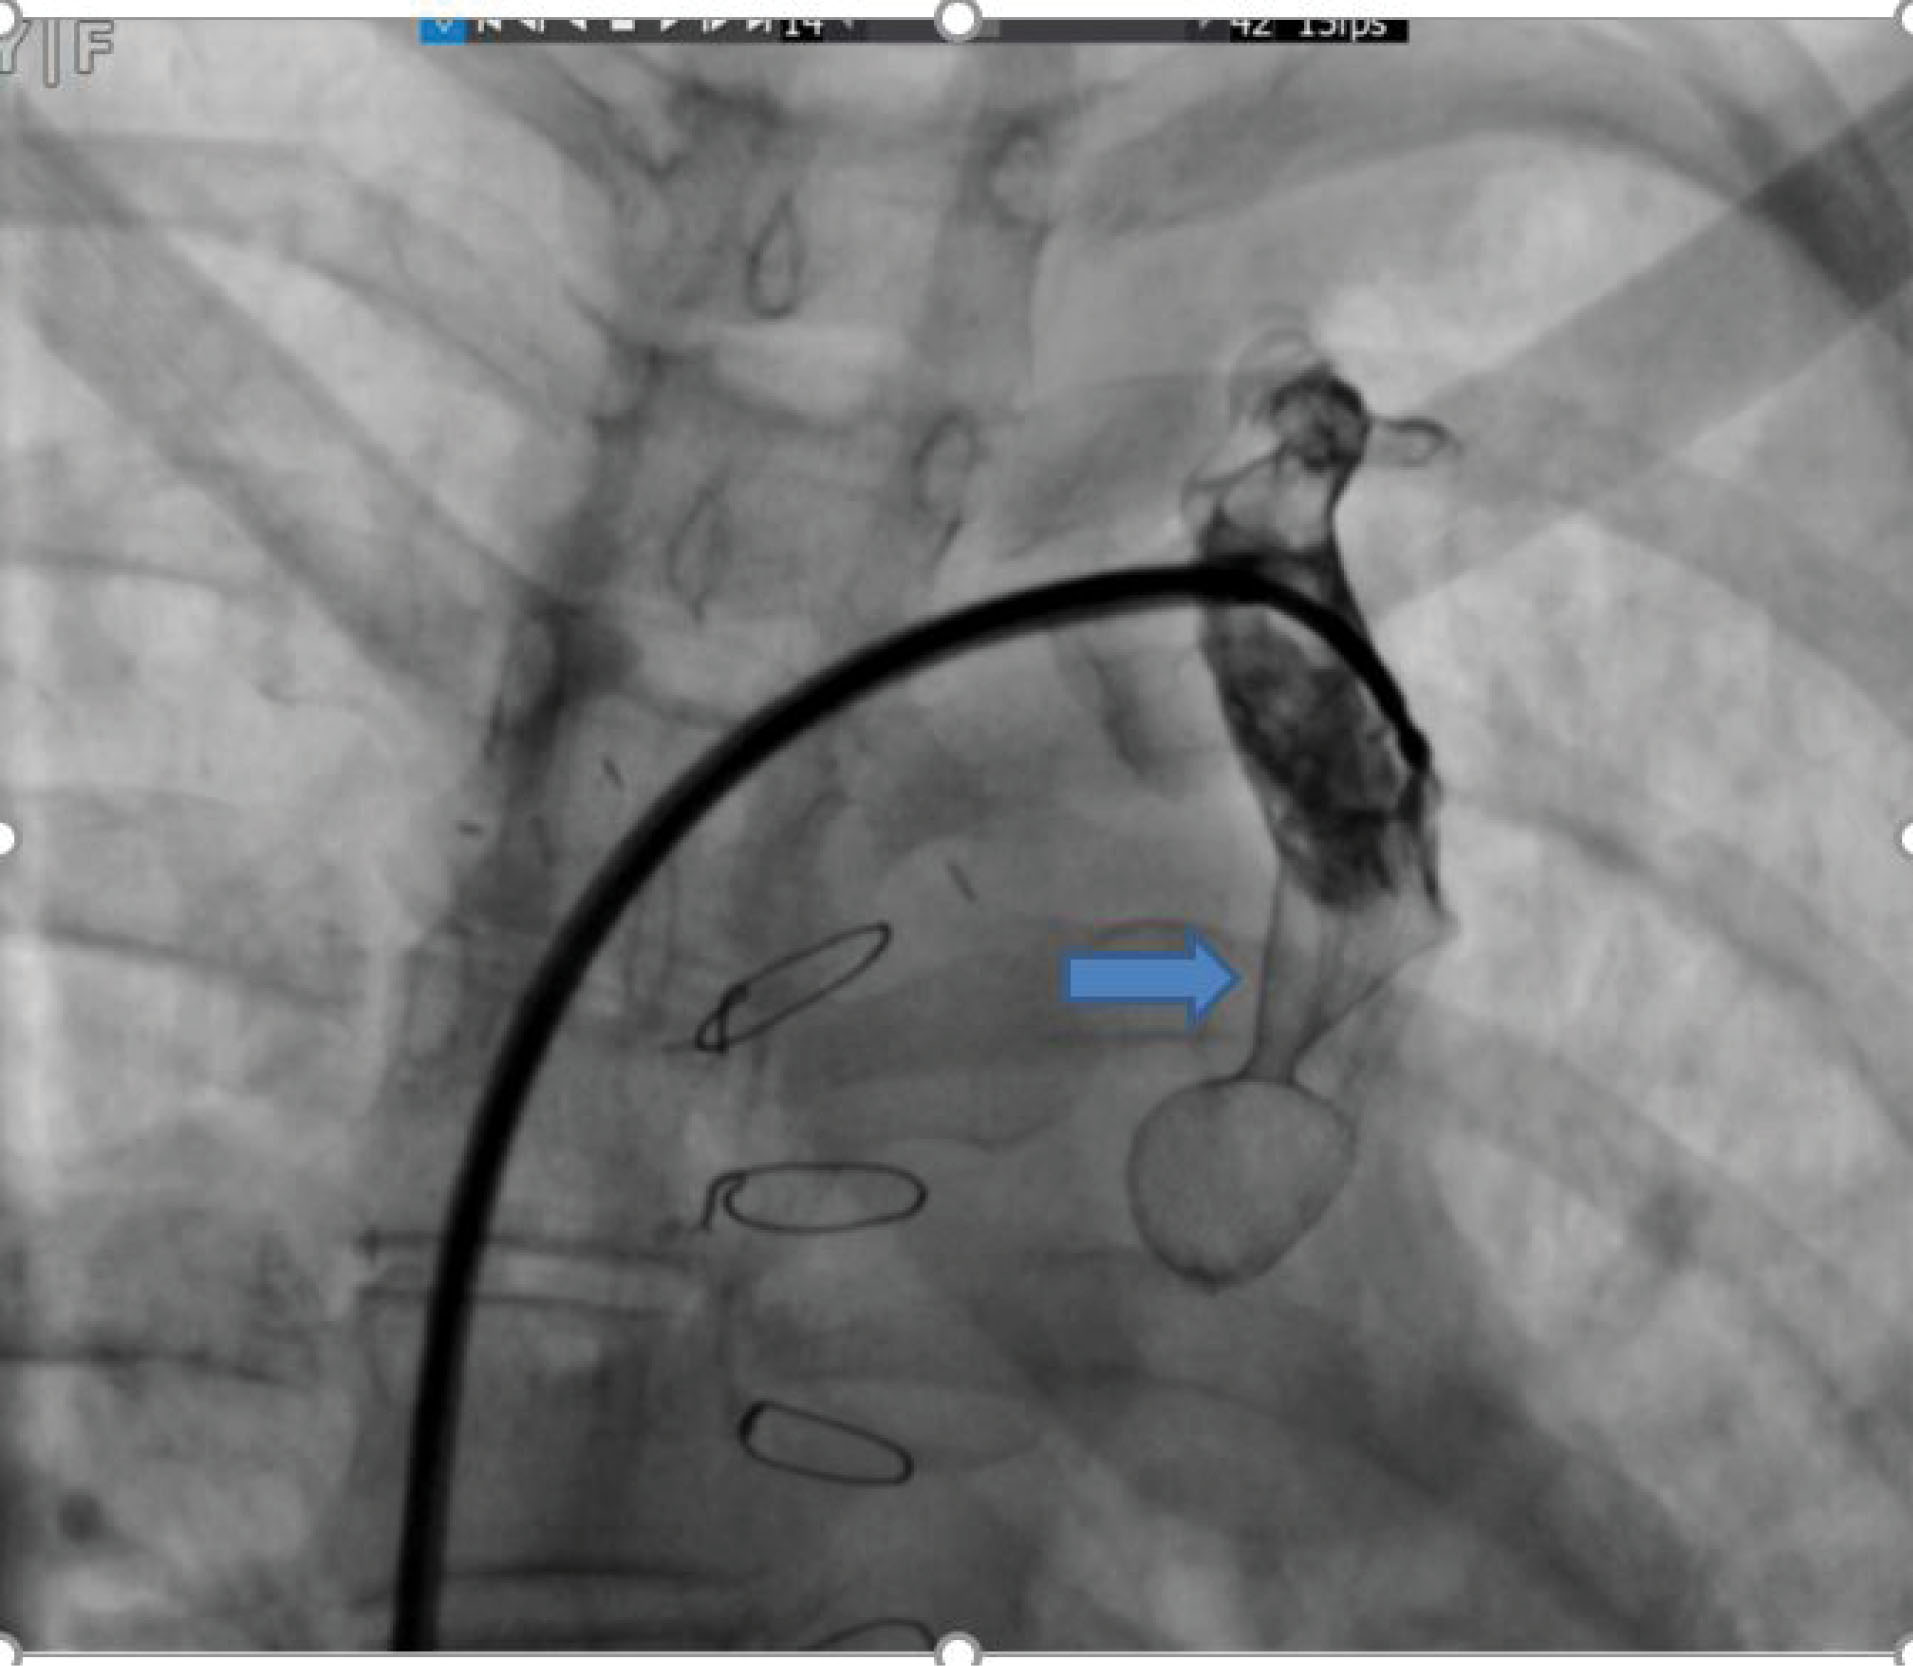

Hemoglobin concentration was 17g/dL. Electrocardiogram showed low voltage, poor R progression and left anterior hemiblock. Contrast trans-thoracic echocardiography (TTE) with an injection of agitated saline from left brachial vein showed a left-sided dilated para-aortic vessel including a blue color descending flow suggested left superior vena cava (LSVC) with a fast entrance of bubbles into the left atrium (). Finally, she underwent cardiac magnetic resonance imaging (CMR) due to cyanosis which revealed the presence of very engorged dilated left lower and left upper pulmonary veins with fistulous connection which left upper pulmonary vein (LUPV) connected to vertical vein and then into an innominate vein and finally SVC. The direction of flow was from SVC to left upper pulmonary vein, left lower pulmonary vein, and left atrium (LA). (). This Fistula was seen as collateral vessels connected proximally to the inferior aspect of innominate vein and distally to the left lower pulmonary vein. There were some connections between the ascending, and descending limbs of these tortuous venous collaterals and these direct connections between venous collateral vessels could explain fast pass of agitated saline into LA during TTE with contrast study and severe cyanosis of the patient. Probably this abnormal connection of LUPV to vertical vein (PAPVC) was not diagnosed before Fontan operation and developed gradually due to the pressure gradient in the Fontan circuit with connection to LLPV. This pressure gradient could result in further dilatation of vertical vein and prominence of collateral vessels which were connected to the inferior aspect of innominate vein. Thus, catheterization was performed () and Femoral vein was cannulated. We passed from IVC to fontan circuit, SVC, innominate and lastly vertical vein. In injection in vertical vein, we found severe engorged and tortoise pulmonary veins, then a long stiff exchange wire (260 cm) with a long LIFETECH delivery sheath 9F passed through fontan circuit to SVC, innominate vein and vertical vein. An ADO device 14*16 mm chosen and deployed at proximal of vertical vein (). After the detachment of device by vertical injection we confirmed proper position of device and small residual flow. The oxygen saturation immediately increased from 80% to 93%. In the first echocardiography performed after device closure, some contrast agents were entered into the left atrium through a right to left shunt, which indicates the presence of a residual shunt. This might be due to the delayed endothelialization of implanted device.

jcvtr-13-364-g004

Figure 4. ADO device at proximal of vertical vein